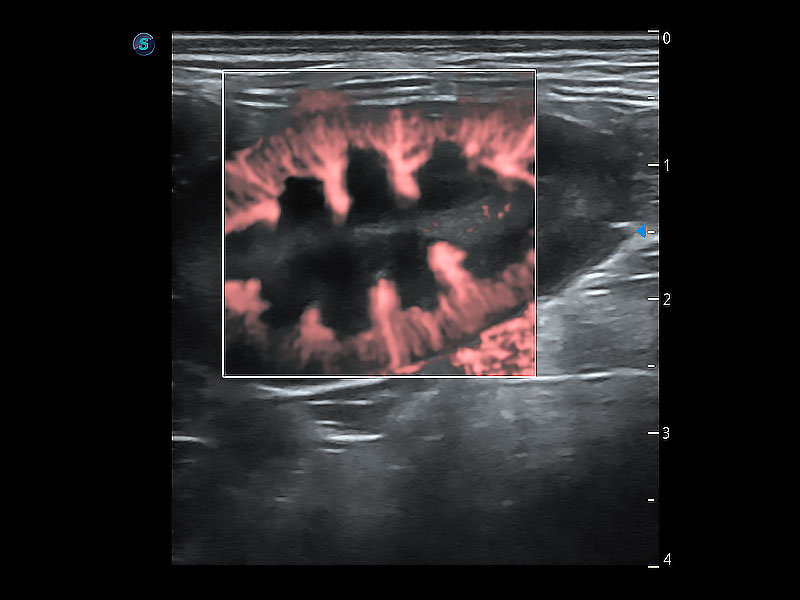

操作简便,无需高频度外力作用即可真实反映组织的形变,快速评估肿瘤良恶性。